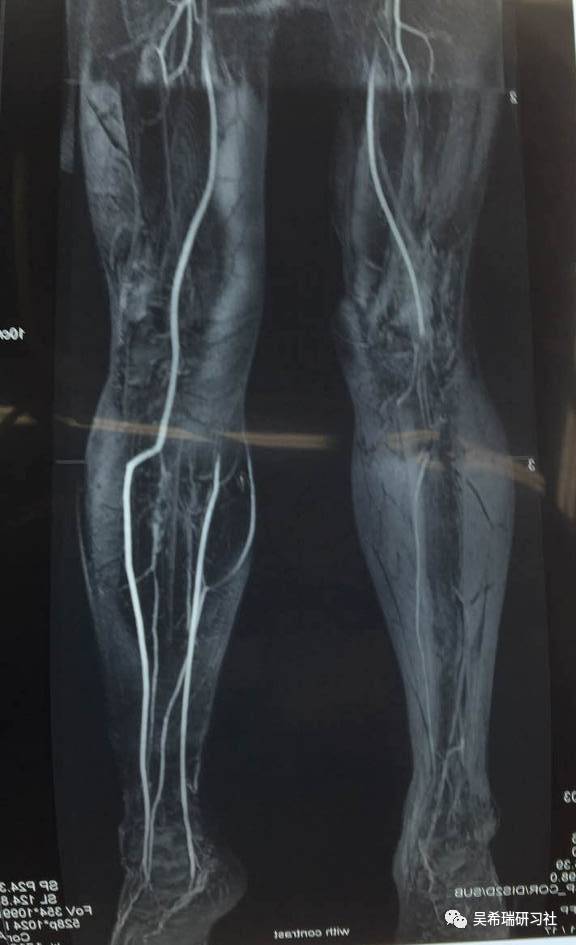

双下肢车祸外伤保肢的理由是足底皮肤好

TIPS:清创&盐水冲洗(不用双氧水)VSD骨水泥技术&开放植骨单边外固定架(下胫腓联合固定)早期下地 生理应力 + 机械应力游离植皮 / 不用皮瓣清创时游离皮质骨去除胫跖骨牵引技术防治&纠正足下垂